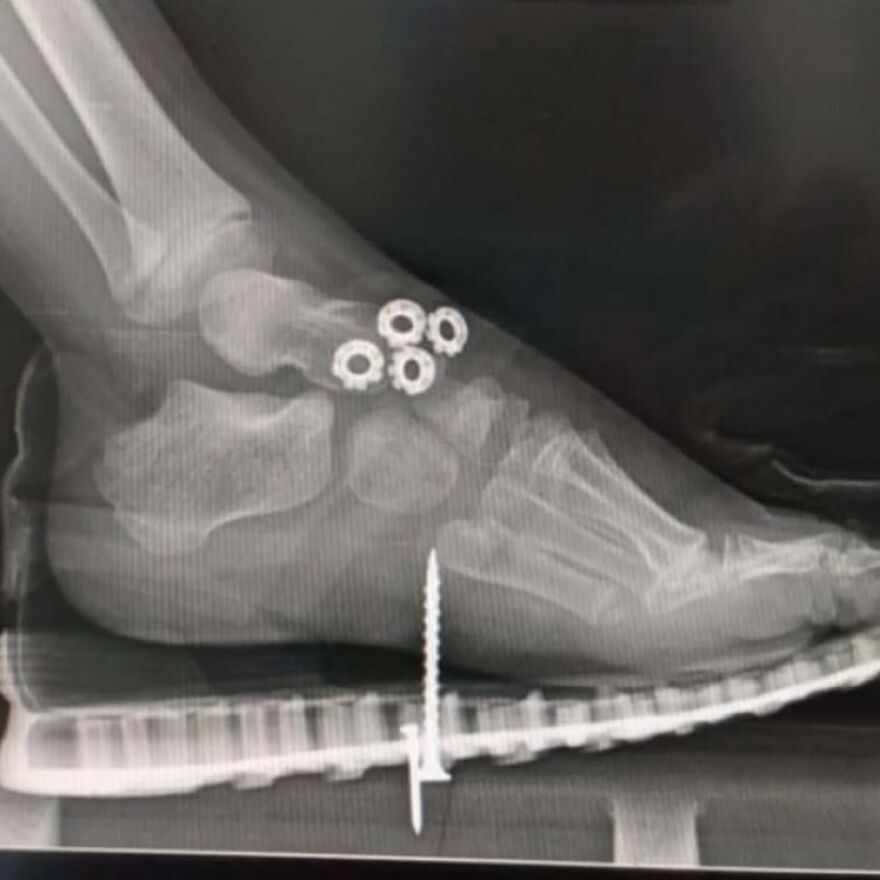

Ilizarov Apparatus

“The Ilizarov apparatus is a type of external fixator used in orthopedic surgery to lengthen bones, reshape limbs, or stabilize fractures. It's a circular frame with rods and rings that attach to the bone through wires, allowing for controlled bone lengthening and bone reconstruction.”